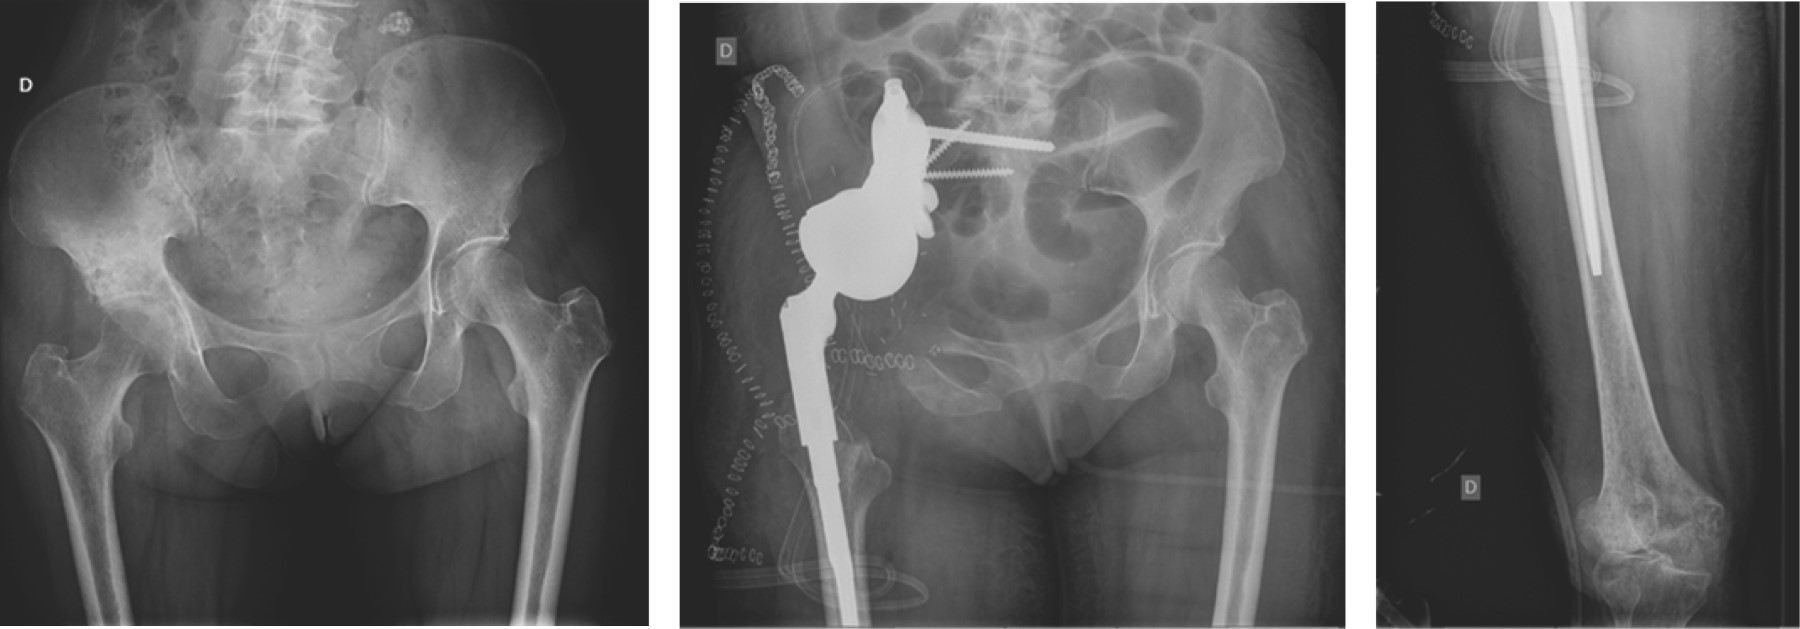

La reconstrucción tras la resección tumoral en los tumores pélvicos (nueve pacientes) se llevó a cabo mediante prótesis de anclaje ilíaco tipo "cucurucho de helado" (Coned®; Stanmore Worldwide Ltd, Elstree, UK) en siete casos y en los dos pacientes restantes se utilizaron prótesis pélvicas a medida con vástagos femorales modulares (Figura 2). En el resto de las localizaciones se utilizaron en todas ellas megaprótesis modulares: megaprótesis de fémur proximal con artroplastía de cadera en 11 casos, de fémur distal con artroplastía de rodilla en tres casos de tumoraciones femorales y dos de tibia proximal y megaprótesis de fémur total en tres pacientes (Figura 3). Con respecto a la fijación, ocho megaprótesis fueron no cementadas (26.7%), mientras que el resto presentaban alguno de los componentes cementados (73.3%). En ocho de los pacientes con resección del fémur proximal se conservó el trocánter mayor mediante reanclaje al vástago femoral para conservar la acción de los rotadores de cadera y en dos pacientes intervenidos mediante megaprótesis de fémur total se mantuvo la porción distal del fémur para mantener la musculatura aductora (Figura 4).

Figura 2

Figura 3

Figura 4